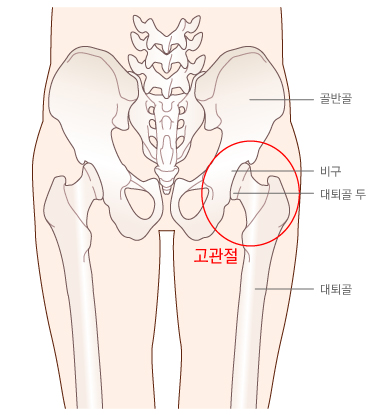

고관절염

[arthritis of the hip joint]

고관절(엉덩이관절)에 발생하는 염증성 질환

정의

고관절에 염증성 병변이 있는 것을 고관절염이라고 하며, 염증이 발생하게 되는 원인은 매우 다양하다. 통증, 관절 운동 범위의 감소 및 파행(절뚝거림)이 주된 증상이며, 관절액의 증가(흔히 관절에 물이 찼다고 표현함), 활액막(관절막을 덮고 있는 얇은 막)의 비후(두꺼워짐), 관절 연골의 두께 감소, 골파괴 및 신생골(새로운 뼈) 생성 등의 소견이 X선 사진이나 자기공명영상(MRI)에서 관찰된다. 증상이 나타나고 진행되는 속도나 심한 정도, 관절 연골이나 뼈에 변화가 나타나는 정도와 속도는 원인에 따라 다르다. 세균 감염에 의한 화농성 고관절염의 경우 병의 진행 정도가 매우 빠르며, 퇴행성(노인성) 고관절염 은 천천히 진행한다.

고관절의 위치